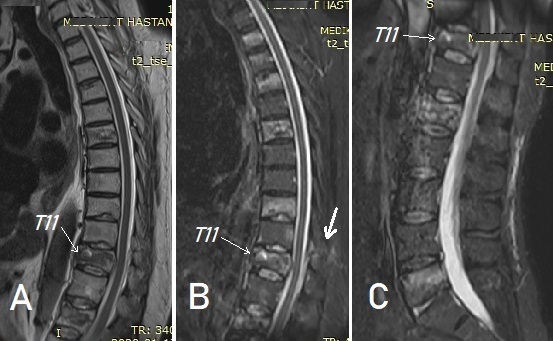

(Torasik ve lomber MRG incelemelerinde, en belirgin olarak STIR

sekanslarında olmak üzere (B ve C) toplam 8 vertebrada kırık

görünmektedir: T2, T3, T4, T6, T9, T11, L1 ve L5.

T11 seviyesinde ayrıca, arka elemanlarda kırık ve kısmi ligaman hasarı

görülmektedir (B, kalın ok).